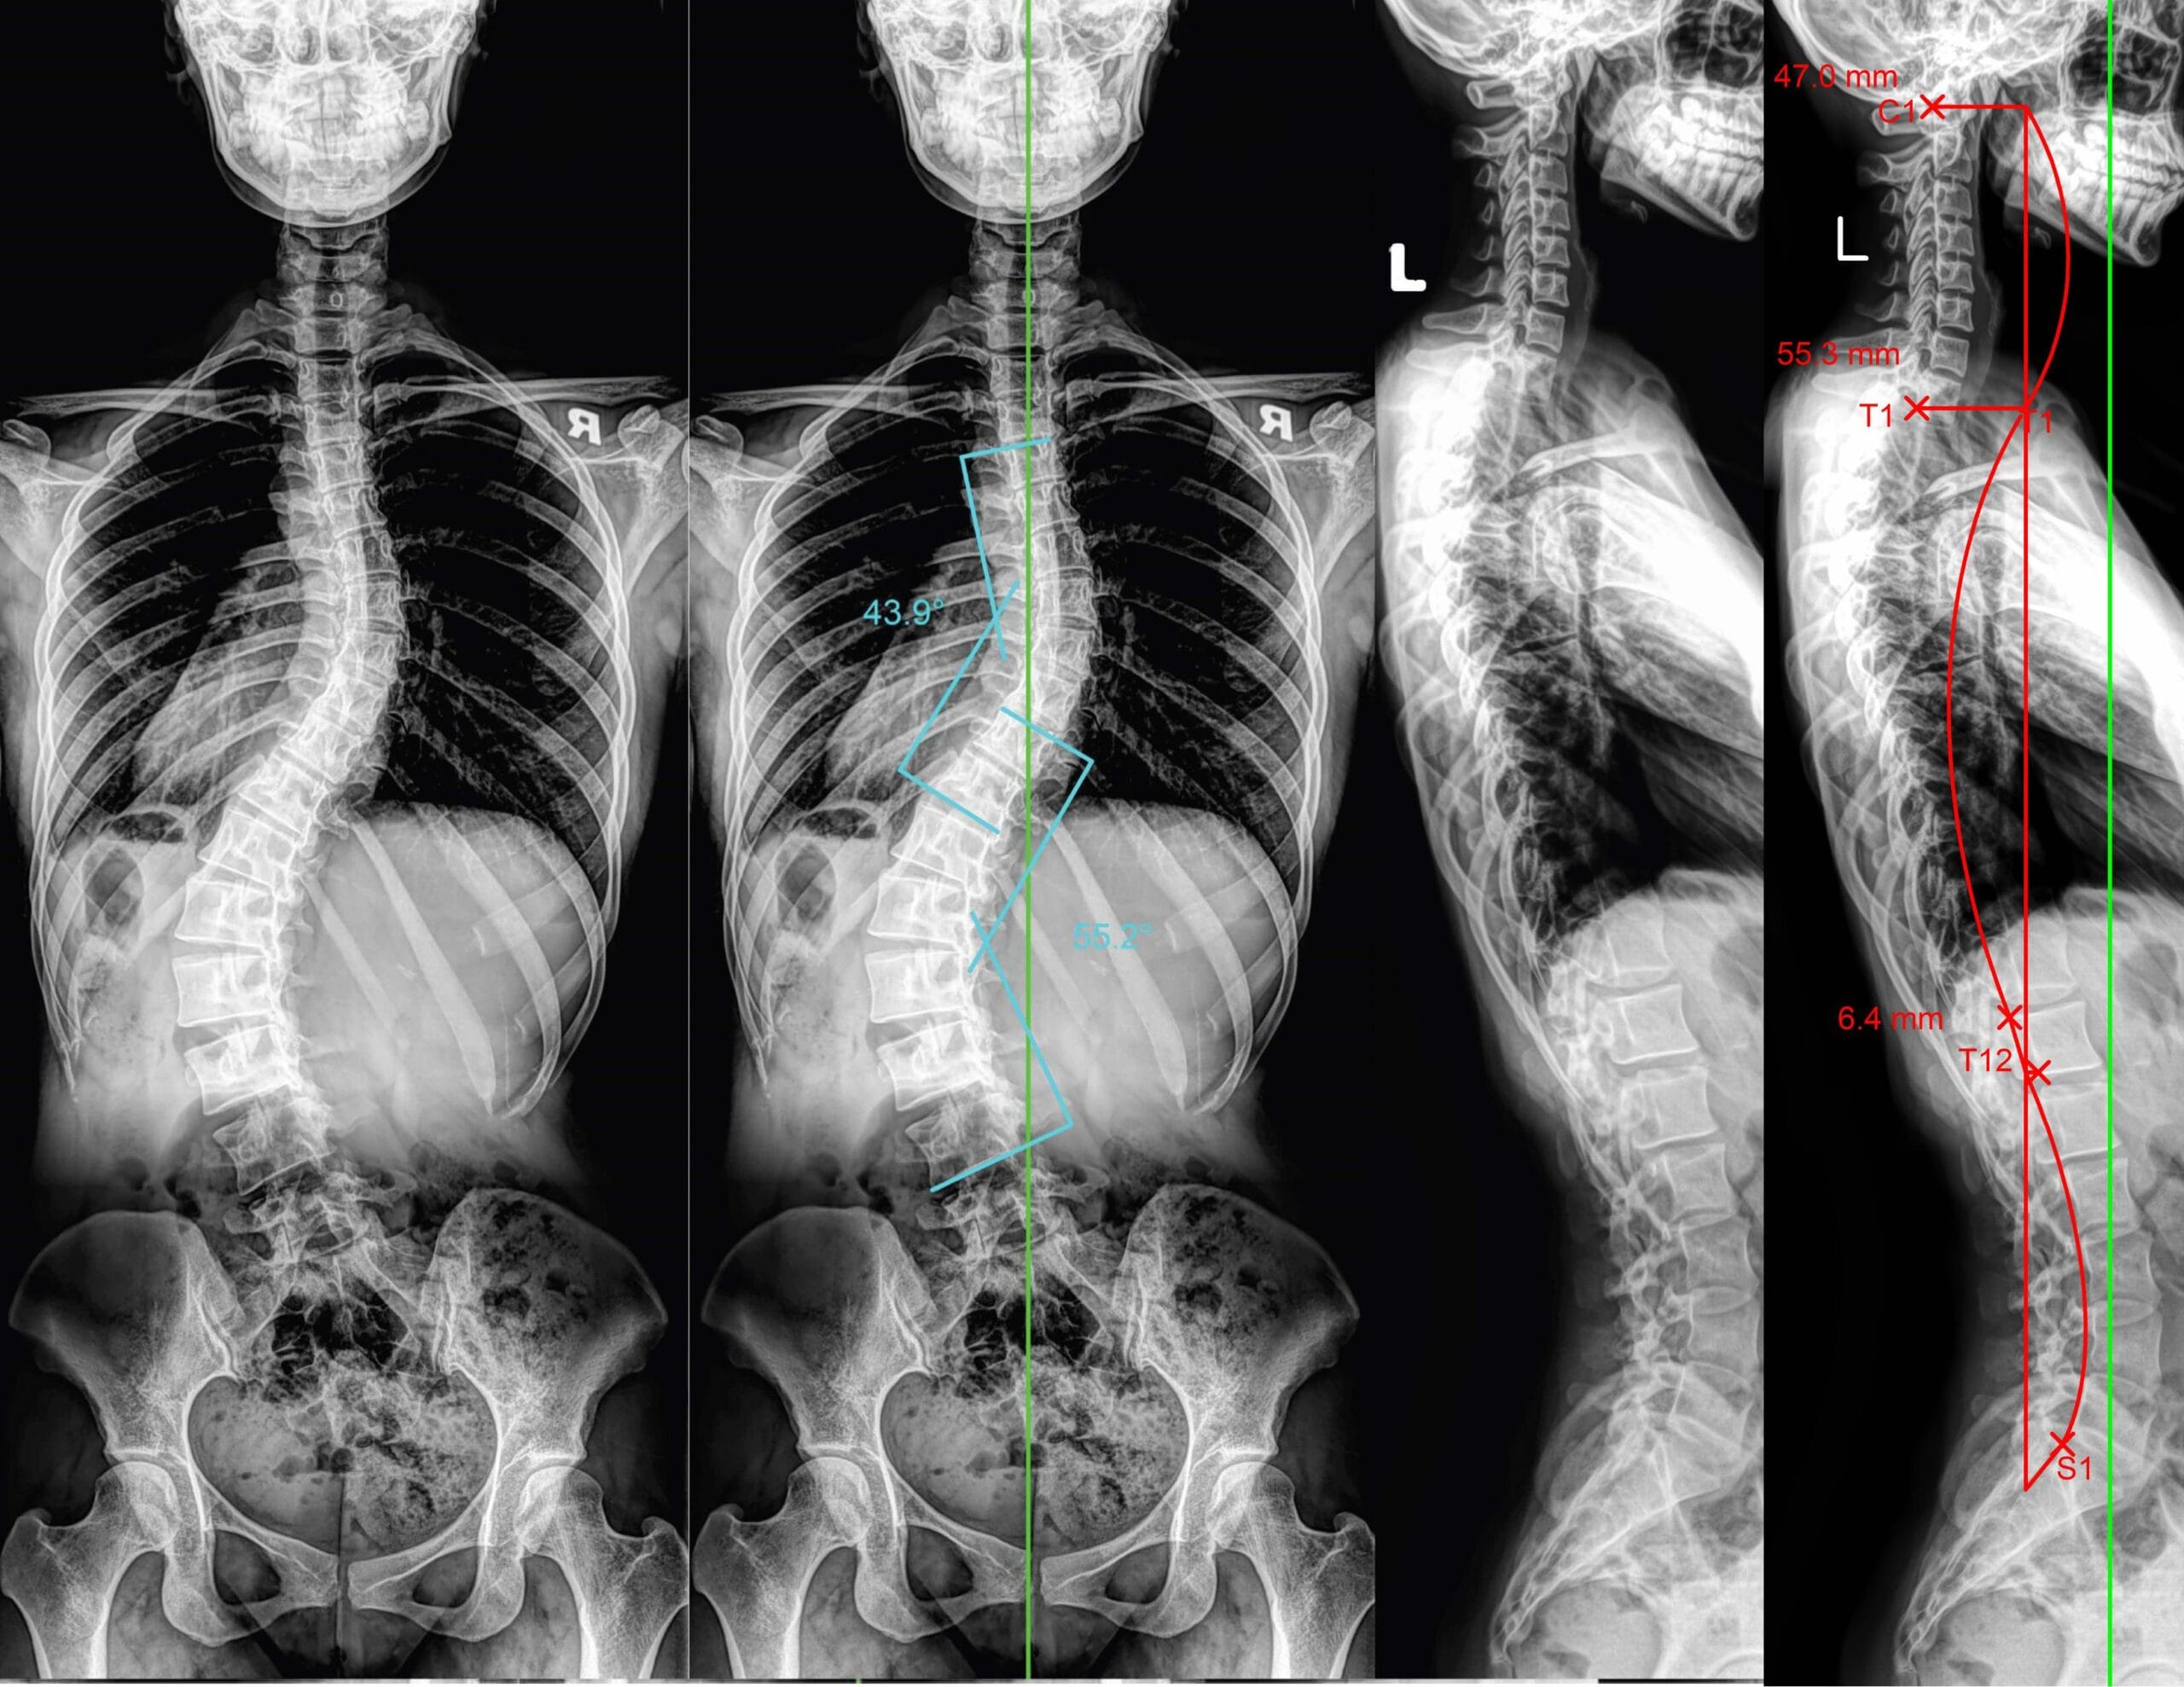

Scoliosis Progression

For individuals who already have a spinal curve, habitual asymmetry like leg crossing can exacerbate scoliosis. Unequal pressure on spinal discs and supporting muscles may accelerate curve progression, potentially increasing the risk of discomfort, nerve compression, or long-term structural changes.

Osso Bone Care utilizes digital X-rays to precisely evaluate spinal and pelvic alignment. This allows practitioners to pinpoint the areas affected by habitual postures like leg crossing and track improvements over time, ensuring that treatments are both targeted and effective.

By addressing the root cause rather than just the symptoms, chiropractic care can reduce chronic back pain, prevent progressive scoliosis, improve posture, and enhance overall spinal health. Regular care combined with mindful sitting habits can help you maintain alignment and prevent further complications from developing.

Not all damage causes immediate pain. You may have subtle asymmetries, like one shoulder slightly higher than the other or a tilted hip, without realizing it. Early detection is key: spinal and pelvic X-ray imaging can reveal misalignments, disc compression, or early signs of degeneration before serious symptoms appear.